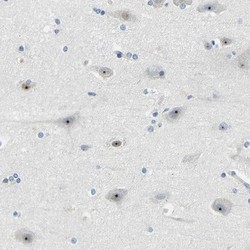

NBP1-85339 IHC

Full details

Method:

Immunohistochemistry